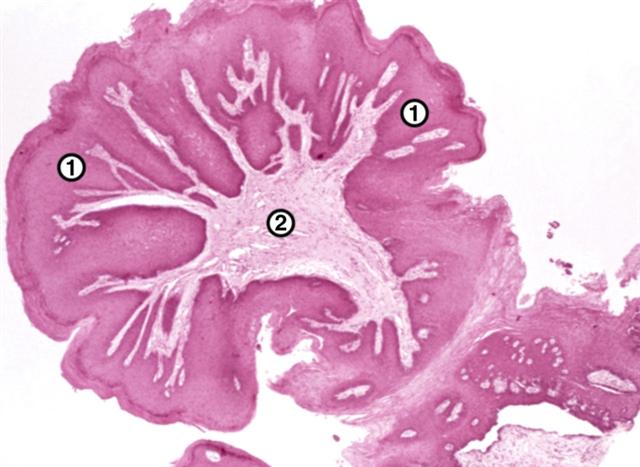

Рис. 1. Микропрепарат папилломы слизистой оболочки полости рта: 1 — поверхность папилломы, покрытая многослойным плоским эпителием; 2 — соединительнотканная строма. Окраска гематоксилином и эозином; ´20.